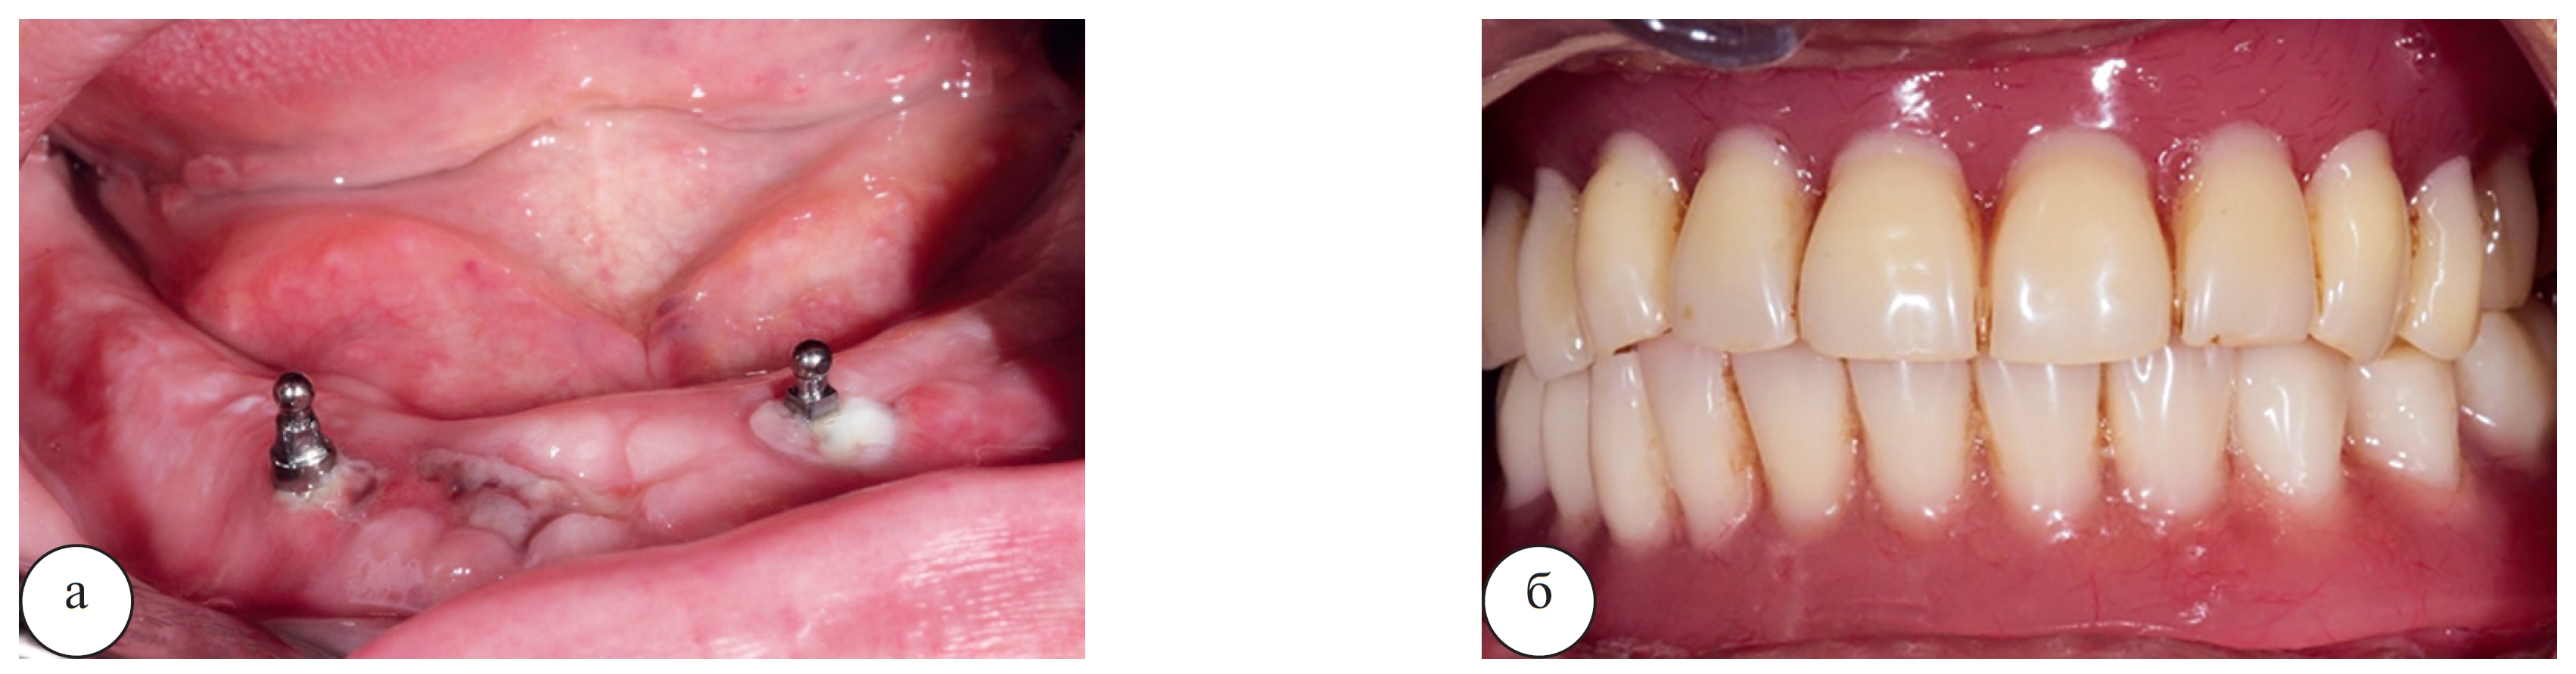

Для съемных ортопедических конструкций необходимо не менее 2 дентальных имплантатов на челюсти. Фиксация протезов при этом осуществляется посредством болл-абатментов, системы локаторов или замковой фиксации на балке. Простота данной методики заключается не только в несложном и малоинвазивном хирургическом протоколе, но и в легкопереносимом послеоперационном периоде для пациента. Так, например применение одноэтапных мини-имплантатов позволяет не только быстро и практически «бескровно» выполнить хирургическую операцию, но и в день операции установить (перебазировать) пациенту ранее изготовленные съемные протезы (рис. 4).

Рис. 4. Этап стоматологической реабилитации пациентки Г. 64 лет, включающий установку 2 одноэтапных миниимплантатов и фиксацию ранее изготовленных съемных акриловых протезов: а – вид в полости рта после удаления зубов и установки мини-имплантатов; б – фиксация протезов осуществлена сразу после операции